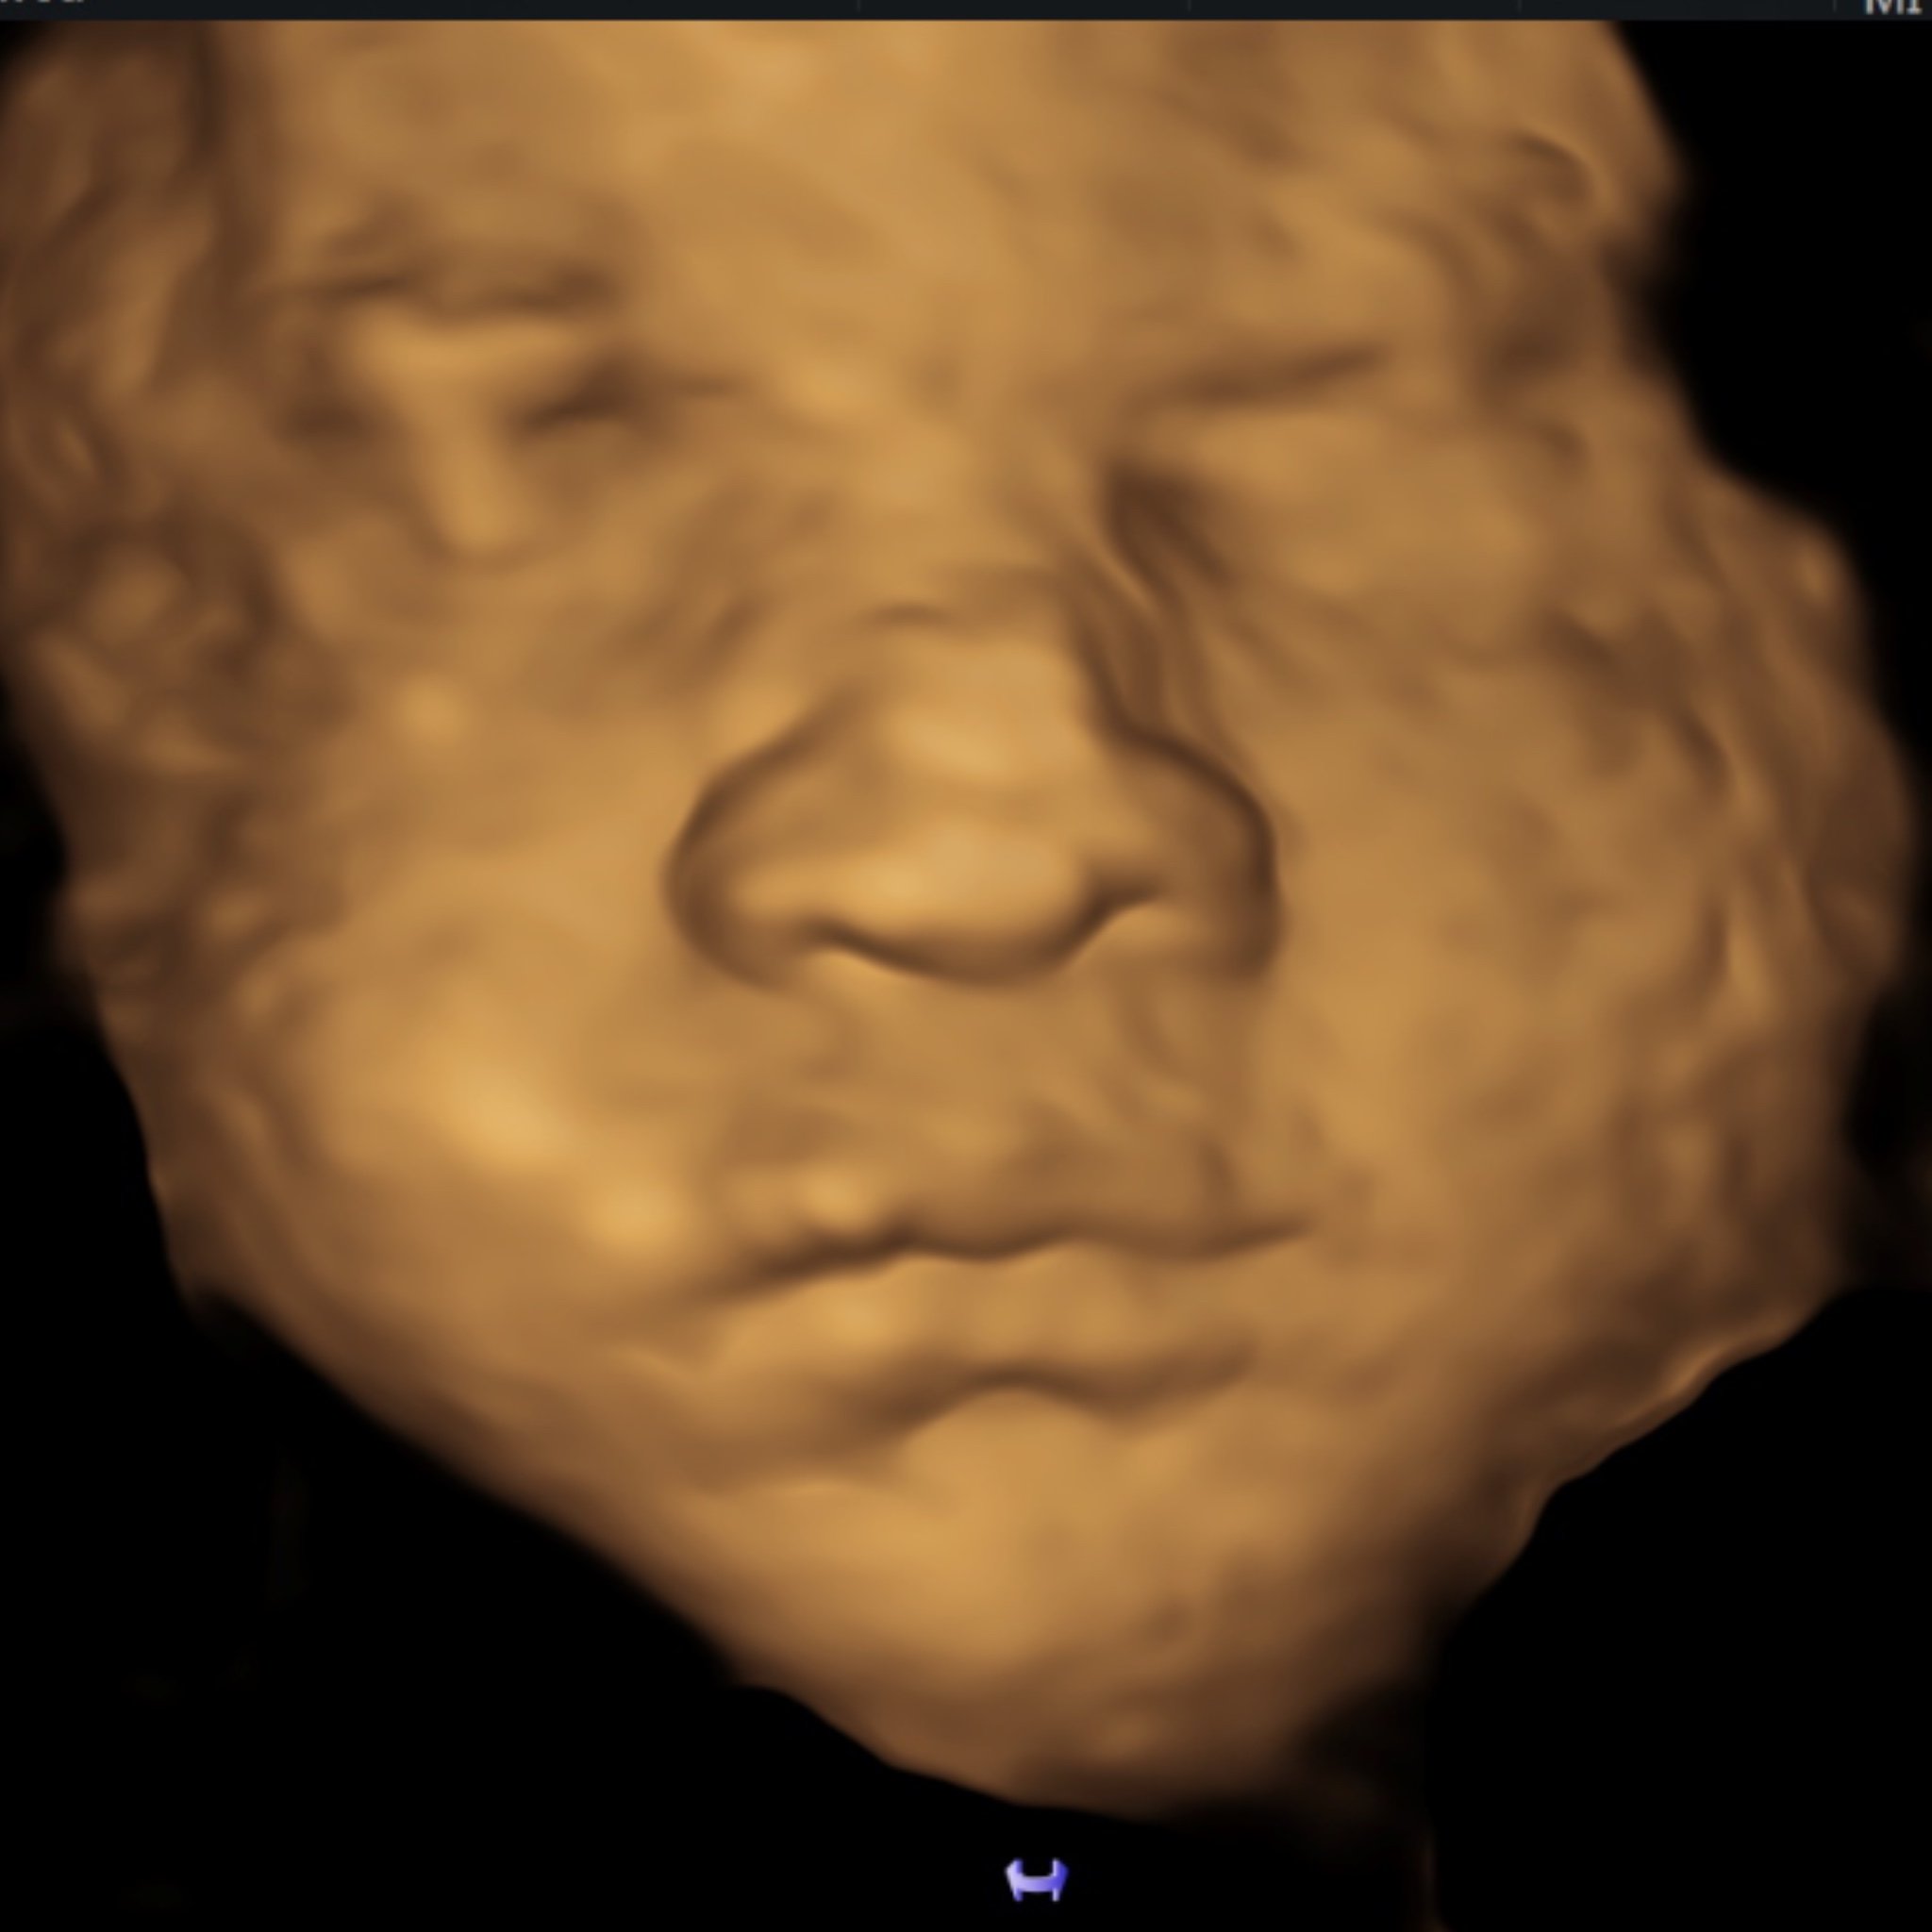

• 10-minute 2D/3D/4D/HD scan

• 8 to 13 weeks pregnant

• Incredible visuals with the latest 3D/4D/HD technology during the 1st trimester

• Heartbeat measurement

• See baby jump, wiggle, hiccup, and move their arms + legs in real time!

• 5 black & white printed images

• All images/videos sent digitally via email